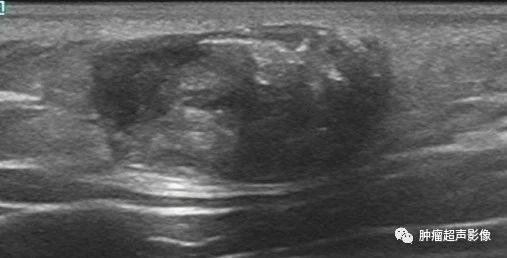

青少年,项部皮肤淡红色,可移动无痛性肿块,皮肤真皮与皮下脂肪层交界处见低回声,边界清,内见点状强回声,周围脂肪回声增强,内见血流,符合典型毛母质瘤的特点。